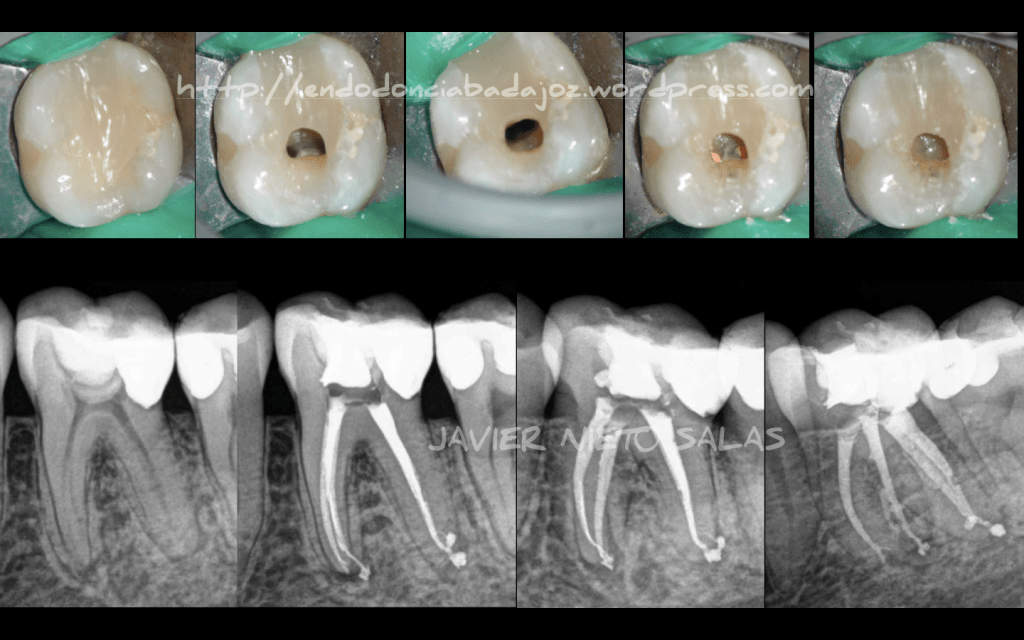

Acude a nuestra consulta un paciente con un tratamiento de conductos realizado hace un par de años, presenta sintomatología, refiere dolor al morder y ,últimamente, también dolor espontáneo.

En las pruebas diagnósticas realizadas, presenta sondaje fisiológico y percusión positiva. Diagnosticamos : Periodontitis Apical Sintomática como consecuencia de una Subobturación (inicialmente fue nuestro diagnóstico, más tarde veríamos que presentaba algún conducto omitido).

El tratamiento fue realizado en una sola sesión, ya que manejamos rápidamente el caso y tuvimos suficiente tiempo para la fase de desinfección. La instrumentación fue con Mtwo hasta un 25/6%, menos el conducto mesio-central (20/6%).

Obturamos con condensación vertical con ola continua de Buchanan modificada y un backfilling con la pistola B&L.

Le haremos una revisión a los 9 meses para ver la evolución.

Pulpitis Irreversible de la pieza 3.6, Instrumentada con Mtwo hasta una conicidad de 25/ 6% (Itsmo Mesial instrumentado hasta un 20/6%). Obturado con condensación Vertical con ola continua. Se han sellado las entradas de los conductos con composite fluido para evitar una filtración coronal. Un saludo

Hola a tod@s!!!! Necrosis Pulpar con periodontitis apical asintomática. Tratamiento en una sola sesión de 90 min de trabajo, con más de 20 min dedicado a la irrigación tras la instrumentación. Se sospechaba de Fractura Vertical , pero no observamos ninguna línea de fisura. Se obturó con condensación Vertical con Ola continua y un backfilling con gutapercha inyectada. Dos años después, se observa un resultado satisfactorio. Feliz Verano!!!!